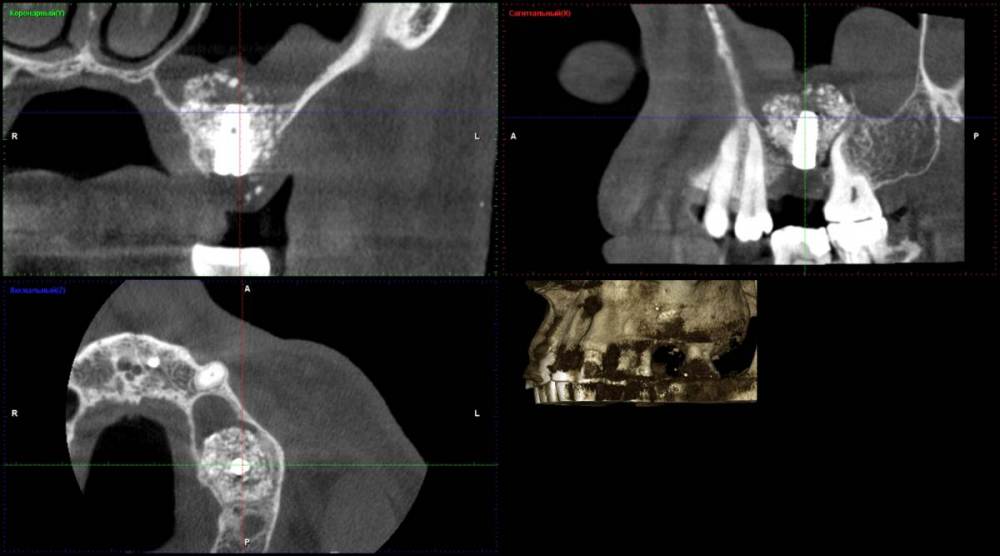

Ponchik Опубликовано 7 апреля, 2021 Поделиться Опубликовано 7 апреля, 2021 Добрый день. В августе прошлого года делал синуслифтинг (биоосс) Месяц назад поставил имплантант. Сегодня пациент пришел с жалобами на небольшую боль в области верхней челюсти. Сначало болело справа, потом слева(где работа) а сегодня прошло. В области имплантата свищ на верхушке гребня. Эксудат (уже чуть-чуть). Думаю имплантант убирать, весь материал убирать (как весь убрать пока не решил). Через полгода новый синуслифтинг и т.д. Но человек слаб и я тешу себя надеждой может не всё пропало? Добавил скрин перед имплантацией и скрин сегодня. На момент имплантации делалось ОПТГ, не информативное. Ссылка на комментарий

Карен Аванесов Опубликовано 10 апреля, 2021 Поделиться Опубликовано 10 апреля, 2021 На стартовом кт. изначально не очень картинка, скорее всего, графт не организован, можно все убрать более предсказуемо будет, можно только имплантат, тогда быть может обойдется без повторного синуслифтинга. Судя по второму кт, жуткого прям такого воспаления нет, если пациент к Вам лоялен, консервативный вариант может иметь место. 1 Ссылка на комментарий